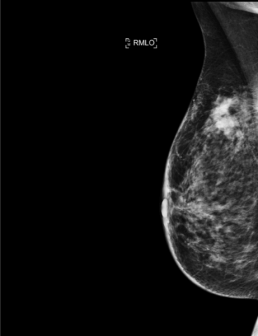

Patiente de 40 ans aux antécédents de carcinome mammaire droit il y a 10 ans – une mammographie de surveillance est effectuée.

Mammoscreen™ détecte un surcroît d’opacité du quadrant supéro-externe du sein droit.